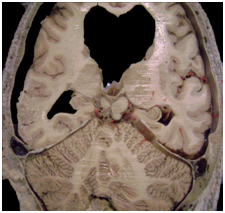

The sigmoid section of the lateral sinus is the terminus for the mastoid emissary vein, whose drainage area includes the mucoperiosteum of the mastoid cells and the mastoid region skin appendages (Figure 2). This explains the septic thrombosis of the lateral sinus due to septic thrombus in the emissary vein during infectious processes of the mastoid (Figure 3 & 4).2‒4

Figure 3 & 4 Right lateral sinus thrombosis in sigmoid section. Anatomic imaging correlation.

Septic thrombi coming from the mastoid emissary vein are the key ethopatogenic mechanism in lateral sinus thrombosis derivated from otomastoiditis, noting that the mastoid emissary vein is the only vein draining to the dural system in the lateral sinus.